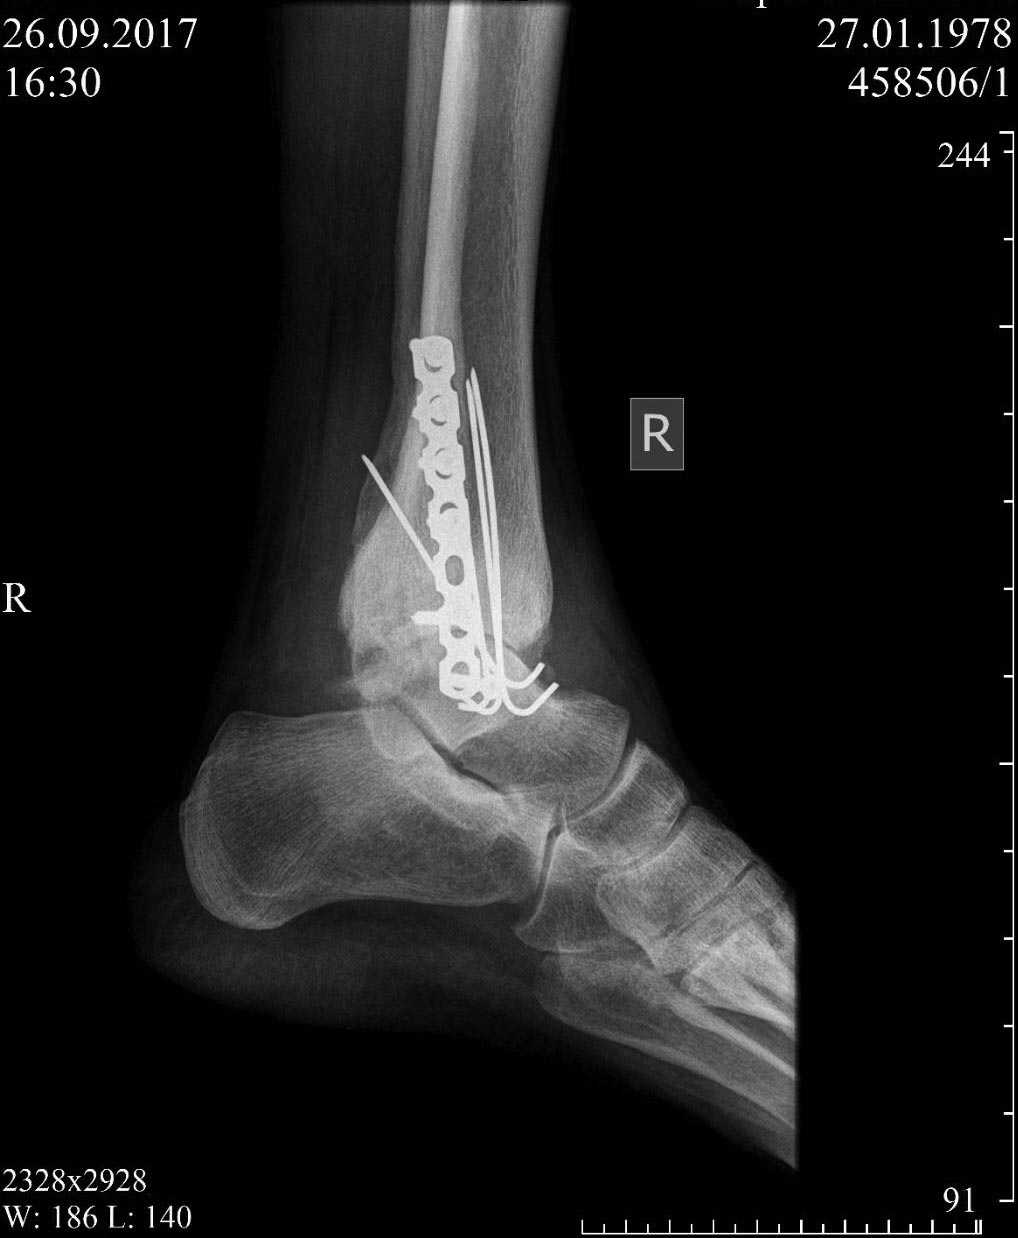

Был нами прооперирован в марте 2016г( устранён подвывих,сустав стабилизирован пластиной -м/б кость и спицами- внутр.лодыжка).

Важно отметить, что в области сустава кожа пигментирована, истончена...( нарушена трофика, осложнения диабета). Заживление п/о ран первичным натяжением.Иммобилизация гипсовым сапожком до 3 мес.В процессе лечения около года не было сращения внутренней лодыжки на 3х спицах(типа ложного сустава). Но пациент с момента снятия гипса до настоящего времени активно двигался, работал в ортезе, ничего не беспокоило.Около месяца тому назад появились боли к концу дня, отечность.

На последнем снимке картина деструкции дистального метаэпифиза большеберцовой кости, протрузия таранной кости, формирующийся подвывих стопы,диабетическая остеоартропатия.Препараты кальция не принимал, не рекомендует нефролог в виду ХПН.

Был первоначальный, теперь промежуточный.

С трудом, но шлет по одному( с телефона, нет возможности форматировать) Ну и ещё один свежий(боковая проекция).